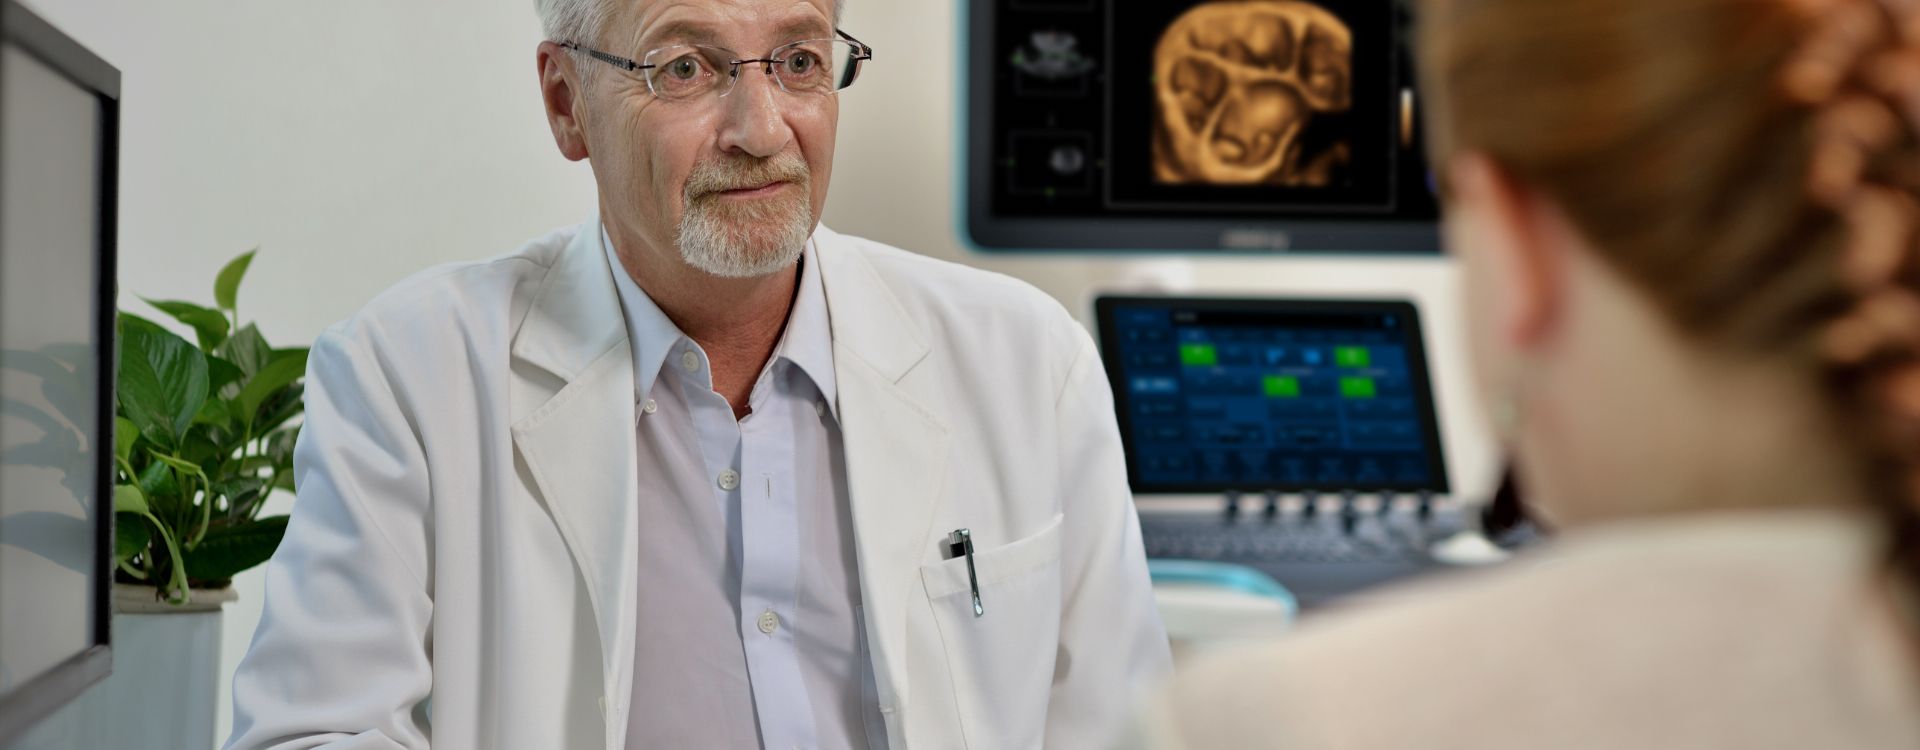

ImĂĄgenes generales

Las soluciones de imĂĄgenes generales de Resona de Mindray ayudan al personal clĂnico a realizar diagnĂłsticos y obtener resultados de tratamiento mĂĄs precisos y eficientes a travĂ©s de sondas para aplicaciones de subdivisiĂłn integrales y herramientas de aplicaciĂłn clĂnica eficientes.

El entorno mĂ©dico actual se ha vuelto mĂĄs complejo, con un mayor nĂșmero de casos y cargas de trabajo difĂciles.

Productos generales de generaciĂłn de imĂĄgenes